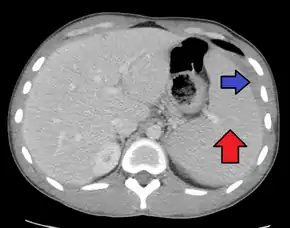

Splenomegaly due to mononucleosis resulting in a subcapsular hematoma

Spleen enlargement is common in the second and third weeks, although this may not be apparent on physical examination. Rarely the spleen may rupture.[24] There may also be some enlargement of the liver.[22] Jaundice occurs only occasionally.[14][25]